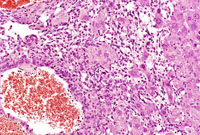

A hemangioma has destroyed the normal hepatic parenchyma. A thrombus is present at the top of the hemangioma; high magnification shows dilated vascular channels lined by flattened endothelial cells. There is minimal atrophy of hepatic cords.